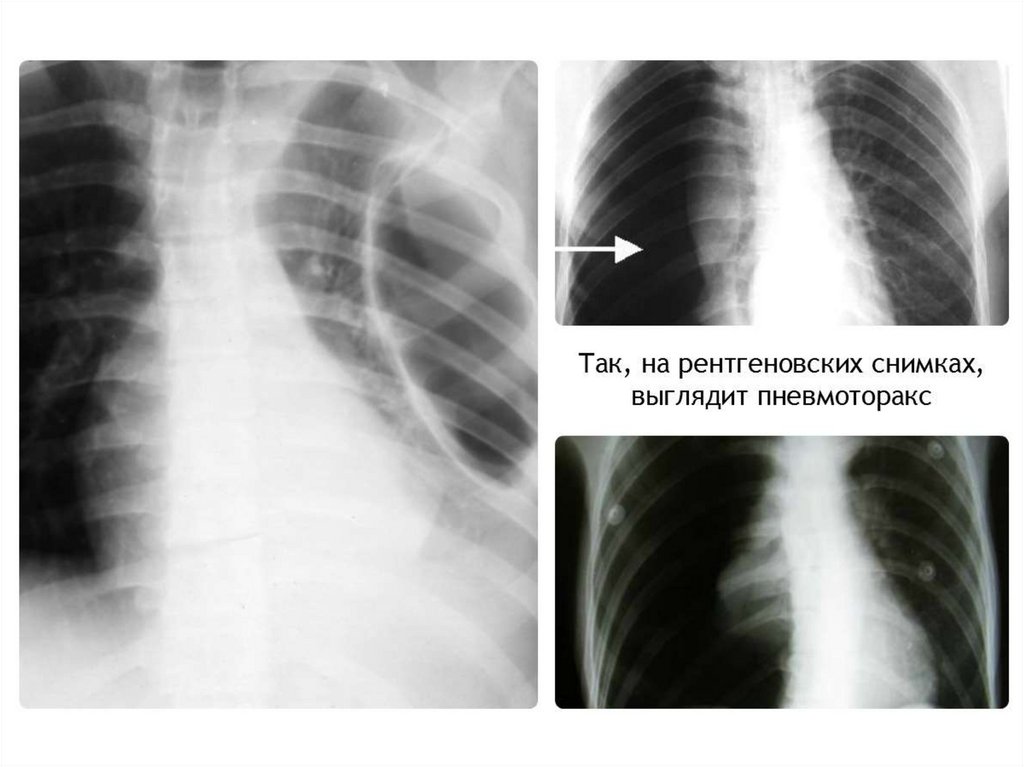

15. Наличие воздуха в плевральной полости

В большинстве случаев пневмоторакс - это

односторонний процесс. Может возникнуть в

результате травмы извне, либо спонтанно при

деструктивных процессах в легких. Имеет 3

механизма – открытый, закрытый, клапанный

(напряженный).

Видимая картина – поджатое к корню легкое,

смещение средостения в другую сторону.

Одностороннее просветление на стороне

поражения.